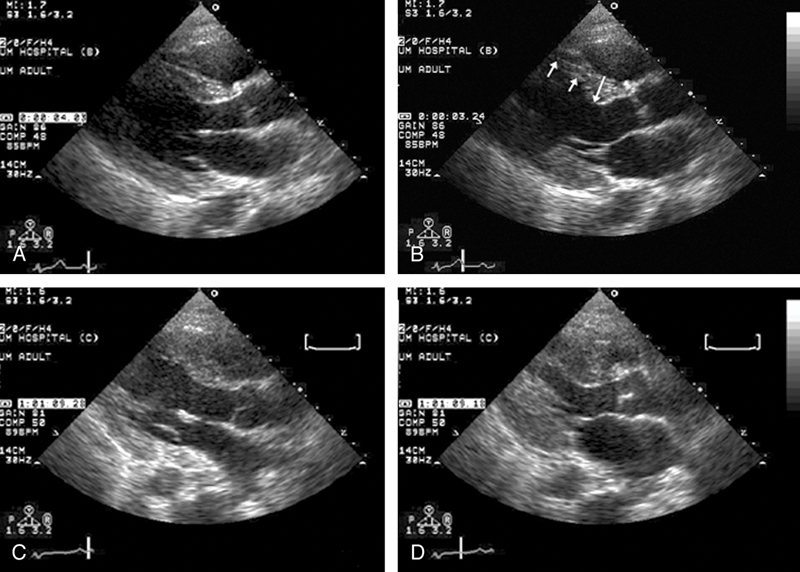

فحوصات تشخيصية لبعض امراض القلب والشرايين التاجية